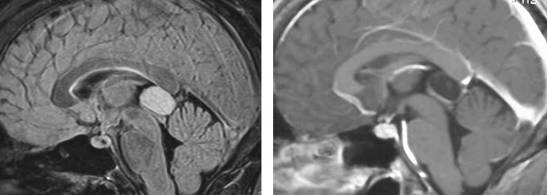

图3. 图示为向四脑室延伸和压迫的蚓部毛细胞星形细胞胶质瘤。肿瘤呈囊性,伴有明显强化的结节。囊壁未见强化,无需手术切除。

图4. 松果体细胞瘤在T2相上表现为高信号,伴有周围强化。松果体细胞瘤一般生长缓慢,偶尔需要手术干预。